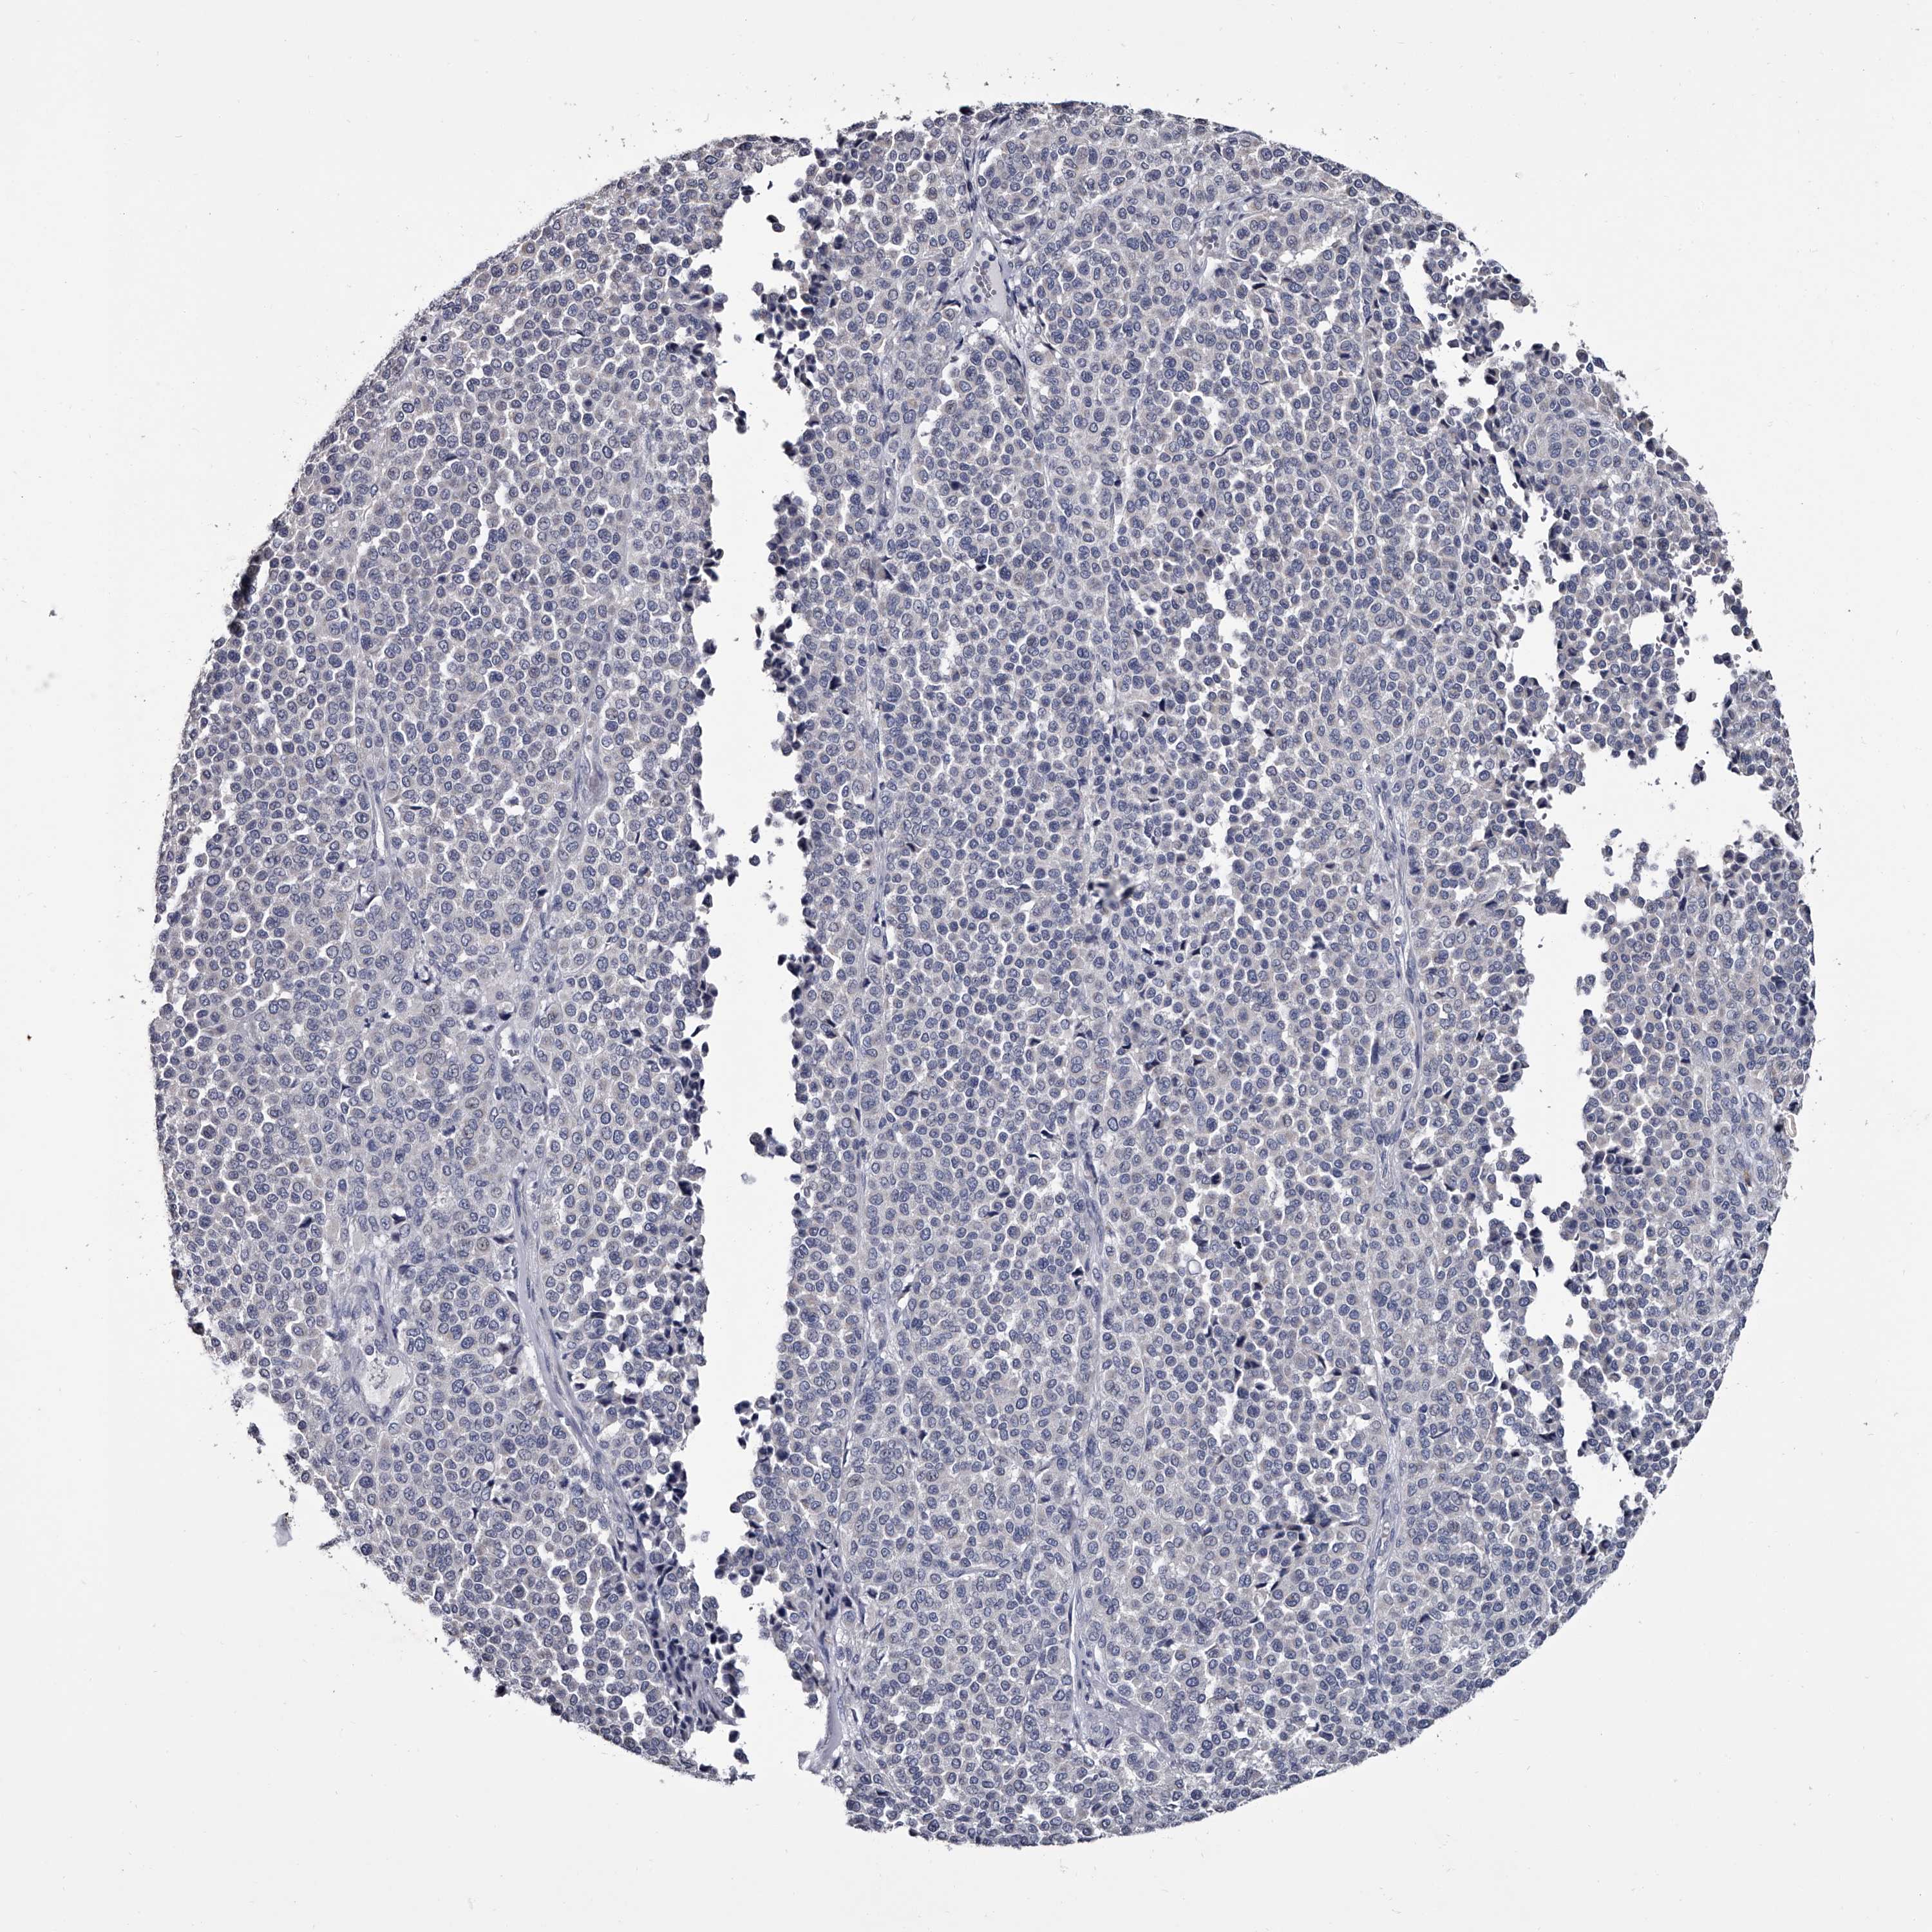

MELANOMA - Protein expressioni

A mouse-over function shows sample information and annotation data. Click on an image to view it in a full screen mode. Samples can be filtered based on level of antibody staining by selecting one or several of the following categories: high, medium, low and not detected. The assay and annotation is described here.

Note that samples used for immunohistochemistry by the Human Protein Atlas do not correspond to samples in the TCGA dataset.

Antibody stainingi

Antibody staining in the annotated cell types in the current human tissue is reported as not detected, low, medium, or high, based on conventional immunohistochemistry profiling in selected tissues. This score is based on the combination of the staining intensity and fraction of stained cells.

Each image is clickable and will lead to virtual microscopy that enables deeper exploration of all samples and also displays staining intensity scores, fraction scores and subcellular localization as well as patient and tissue information for each sample.

Antibody HPA029386

Antibody HPA029387

Malignant melanoma, NOS

Malignant melanoma, Metastatic site